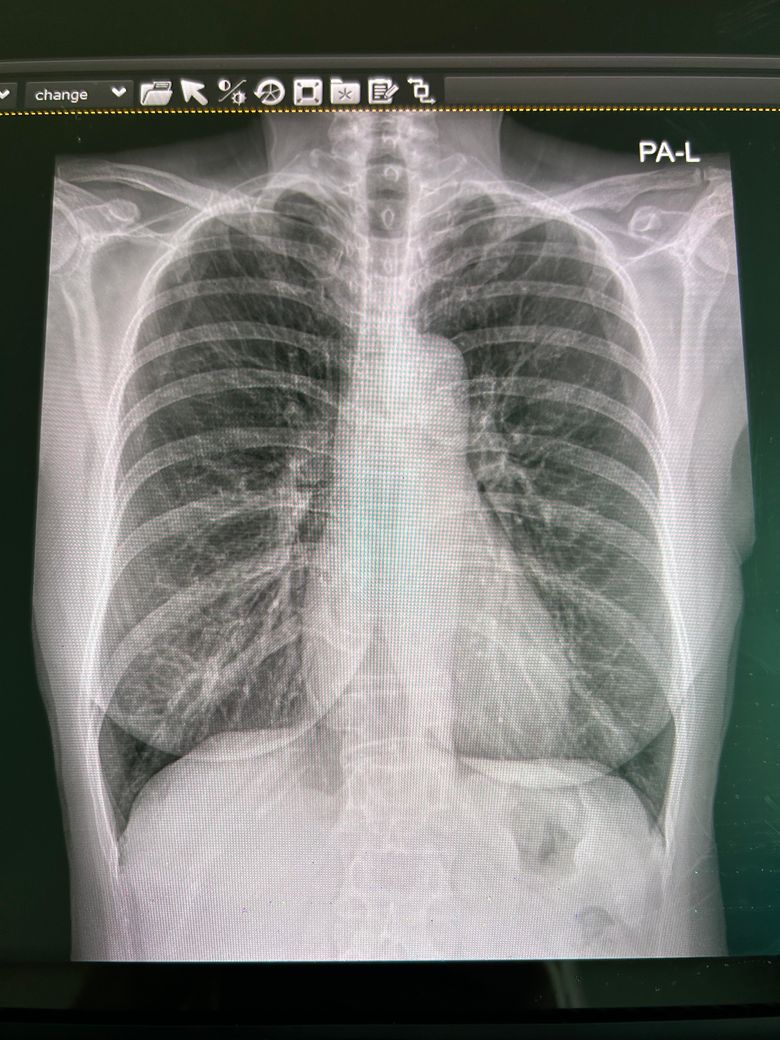

기침이 한달째고 독한 항생제를 먹어도 안나서 폐엑스레이를 찍었는데 좀더 큰병원을 가봐야할까요?

엑스레이상 문제가 있는 부분이 있나요?

기관지염이라고 하는데

엑스레이 찍은 사진입니다~

엑스레이상으로는 기침을 유발할 만한 특이 병변은 없는 것으로 판단 됩니다. 증상이 지속되신다면 CT등으로 정밀검사를 받아보시는 것도 도움이 되겠습니다. 감기이후 기관지과민성과 후비루로 2달이상 잔기침이 지속되는 경우도 있습니다

흉부 X-ray는 큰 이상 없어 보입니다. 항생제도 충분히 써도 효과가 없다면 기관지염 가능성도 떨어진다고 봐야 합니다. 후비루 증후군이나 천식, 역류성 식도염에 대한 치료도 해보시는 것이 좋을 것 같습니다.